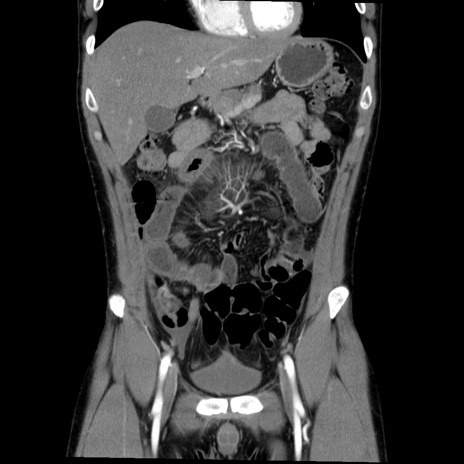

症例36(冠状断像)

【症例】20歳代 男性

【主訴】心窩部痛

【現病歴】今朝より上腹部痛あり。一旦軽快していたが再度出現したため救急要請。昨日夕に白身の魚を含む刺身を食べた。

【身体所見】BP 136/89mmHg、HR 74/min、BT 37.0℃、腹部:膨満、軟、心窩部に圧痛あり。反跳痛なし、筋性防御なし、腸雑音やや亢進あり。

【データ】WBC 17700、CRP 0.48